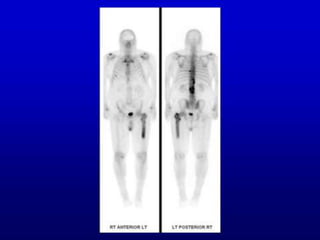

• #5 For simplicity, my main examples will be from nuclear medicine bone images. Here is a two-dimensional bone scan, anterior and posterior, that is, front and back. We don’t have difficulty telling which side is which, because structures like the sternum or breast bone, are better seen on the anterior view and vertebrae, that is, the spine, on the posterior view. These are made using a detector, which shows best what is closest to it. So when it is in front of the patient, we see the breast bone well, but the signals from the spine are reduced by distance and the shadow of the tissues in front of it. Vice versa for the posterior view. This is the femur, the long bone in the leg. Now, by convention, we view the images as though looking at the patient. This femur has a stronger signal that its mate, meaning he has lesion, probably metastatic cancer, in the femur and we can say with confidence that it is the left femur. Note the sacroiliac joints, seen best on the posterior view. The next illustrative case will have a lesion in the sacroiliac joint.

• #12 I’ll try not to be too, too technical, but I do want to explain some of the basis for nuclear medicine scans. We inject radioactive isotopes in people, and there are 2 kinds, both of which undergo radioactive decay, one kind sending out one ray at a time, the other 2 simultaneous rays, or more specifically, photons. The first kind can produce either a 2D image, like the regular bone scan that I showed you first, or 3D images called SPECT. Here’s an illustration for single photon. The photon comes out of the body, here, and hits the detector, here, and an image gets formed. If you ever got such a bone scan, the injected substance was, likely as not, called technetium-99m methylene diphosphonate. This diagram is for PET scan, showing 2 photons going out to detectors, in opposite directions, with images then formed. That kind of bone scan is less common, but was the most suitable for my talk, and the injected substance is fluorine-18 in the form of fluoride, like for your teeth. Incidentally, this is also not the most common kind of PET scan. So, again, the first kind can provide a 3-D scan sometimes, called SPECT, the second kind, PET, is always 3D.

• #29 It’s the same case, but with a difference. Something called depth weighting has been applied, and I’ll explain that. As a result, now you can tell anterior from posterior, and are more likely to see the display as rotating counterclockwise, which corresponds with the true story of the patient, whose lesion is on the right, not the left.

• #30 To illustrate re anterior and posterior. Remember, I said that the original ambiguity occurred because the anterior and posterior images were the same, except for one being the mirror image of the other. This is a MIP, in which that situation has been changed. The anterior and posterior look different. Now you see the spine well in the posterior and the breastbone well in the anterior. Show that. Remember, in the first bone scan that I showed, the one in 2D, anterior and posterior looked different because of distance and the shadow of the tissues in between. In the modified MIP that I am showing you here, the computer has put in the shadows artificially, by the process called depth weighting. If you now see the sacroiliac lesion as being on the right, it is what is true for the patient, because you are now better able to perceive the movie as going counterclockwise rather than clockwise

• #31 You might wonder, “Will a MIP cause the physician to make a mistake?” It should not, because his or her ultimate source of truth will be a cross-sectional image, here a so-called transaxial image (illustrate a slice) which follows the universal convention regarding anterior, posterior, right and left. This is anterior, this is posterior, this is left and this is right. So the abnormality is on the right. Not that physicians reading these scans can’t make mistakes! They can.